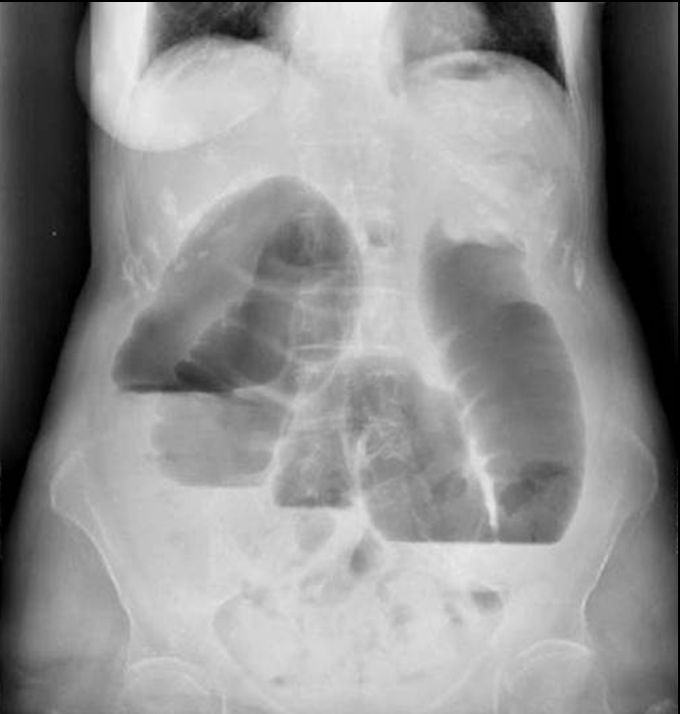

• Plain abdominal radiographs are usually sufficient to raise suspicion for bowel obstruction. In most cases, the radiologic appearance is indicative of the level of the blockage (stomach, small or large bowel). Mechanical obstruction can be incomplete but also it can become complete as the passage function wears off in the strain. Clinical data and patient history (previous abdominal surgery, medication, cancerous state etc.) are all important details in order to help to differentiate the types of obstruction from one another.

21. Right image: plain abdominal X-ray showing distended bowel loops, with wide air-fluid levels. Left image: plain abdominal radiograph showing distended colon until the sigmoid segment, with wide air-fluid levels. The obstruction is most likely to be at the level of the sigmoid or the rectum.